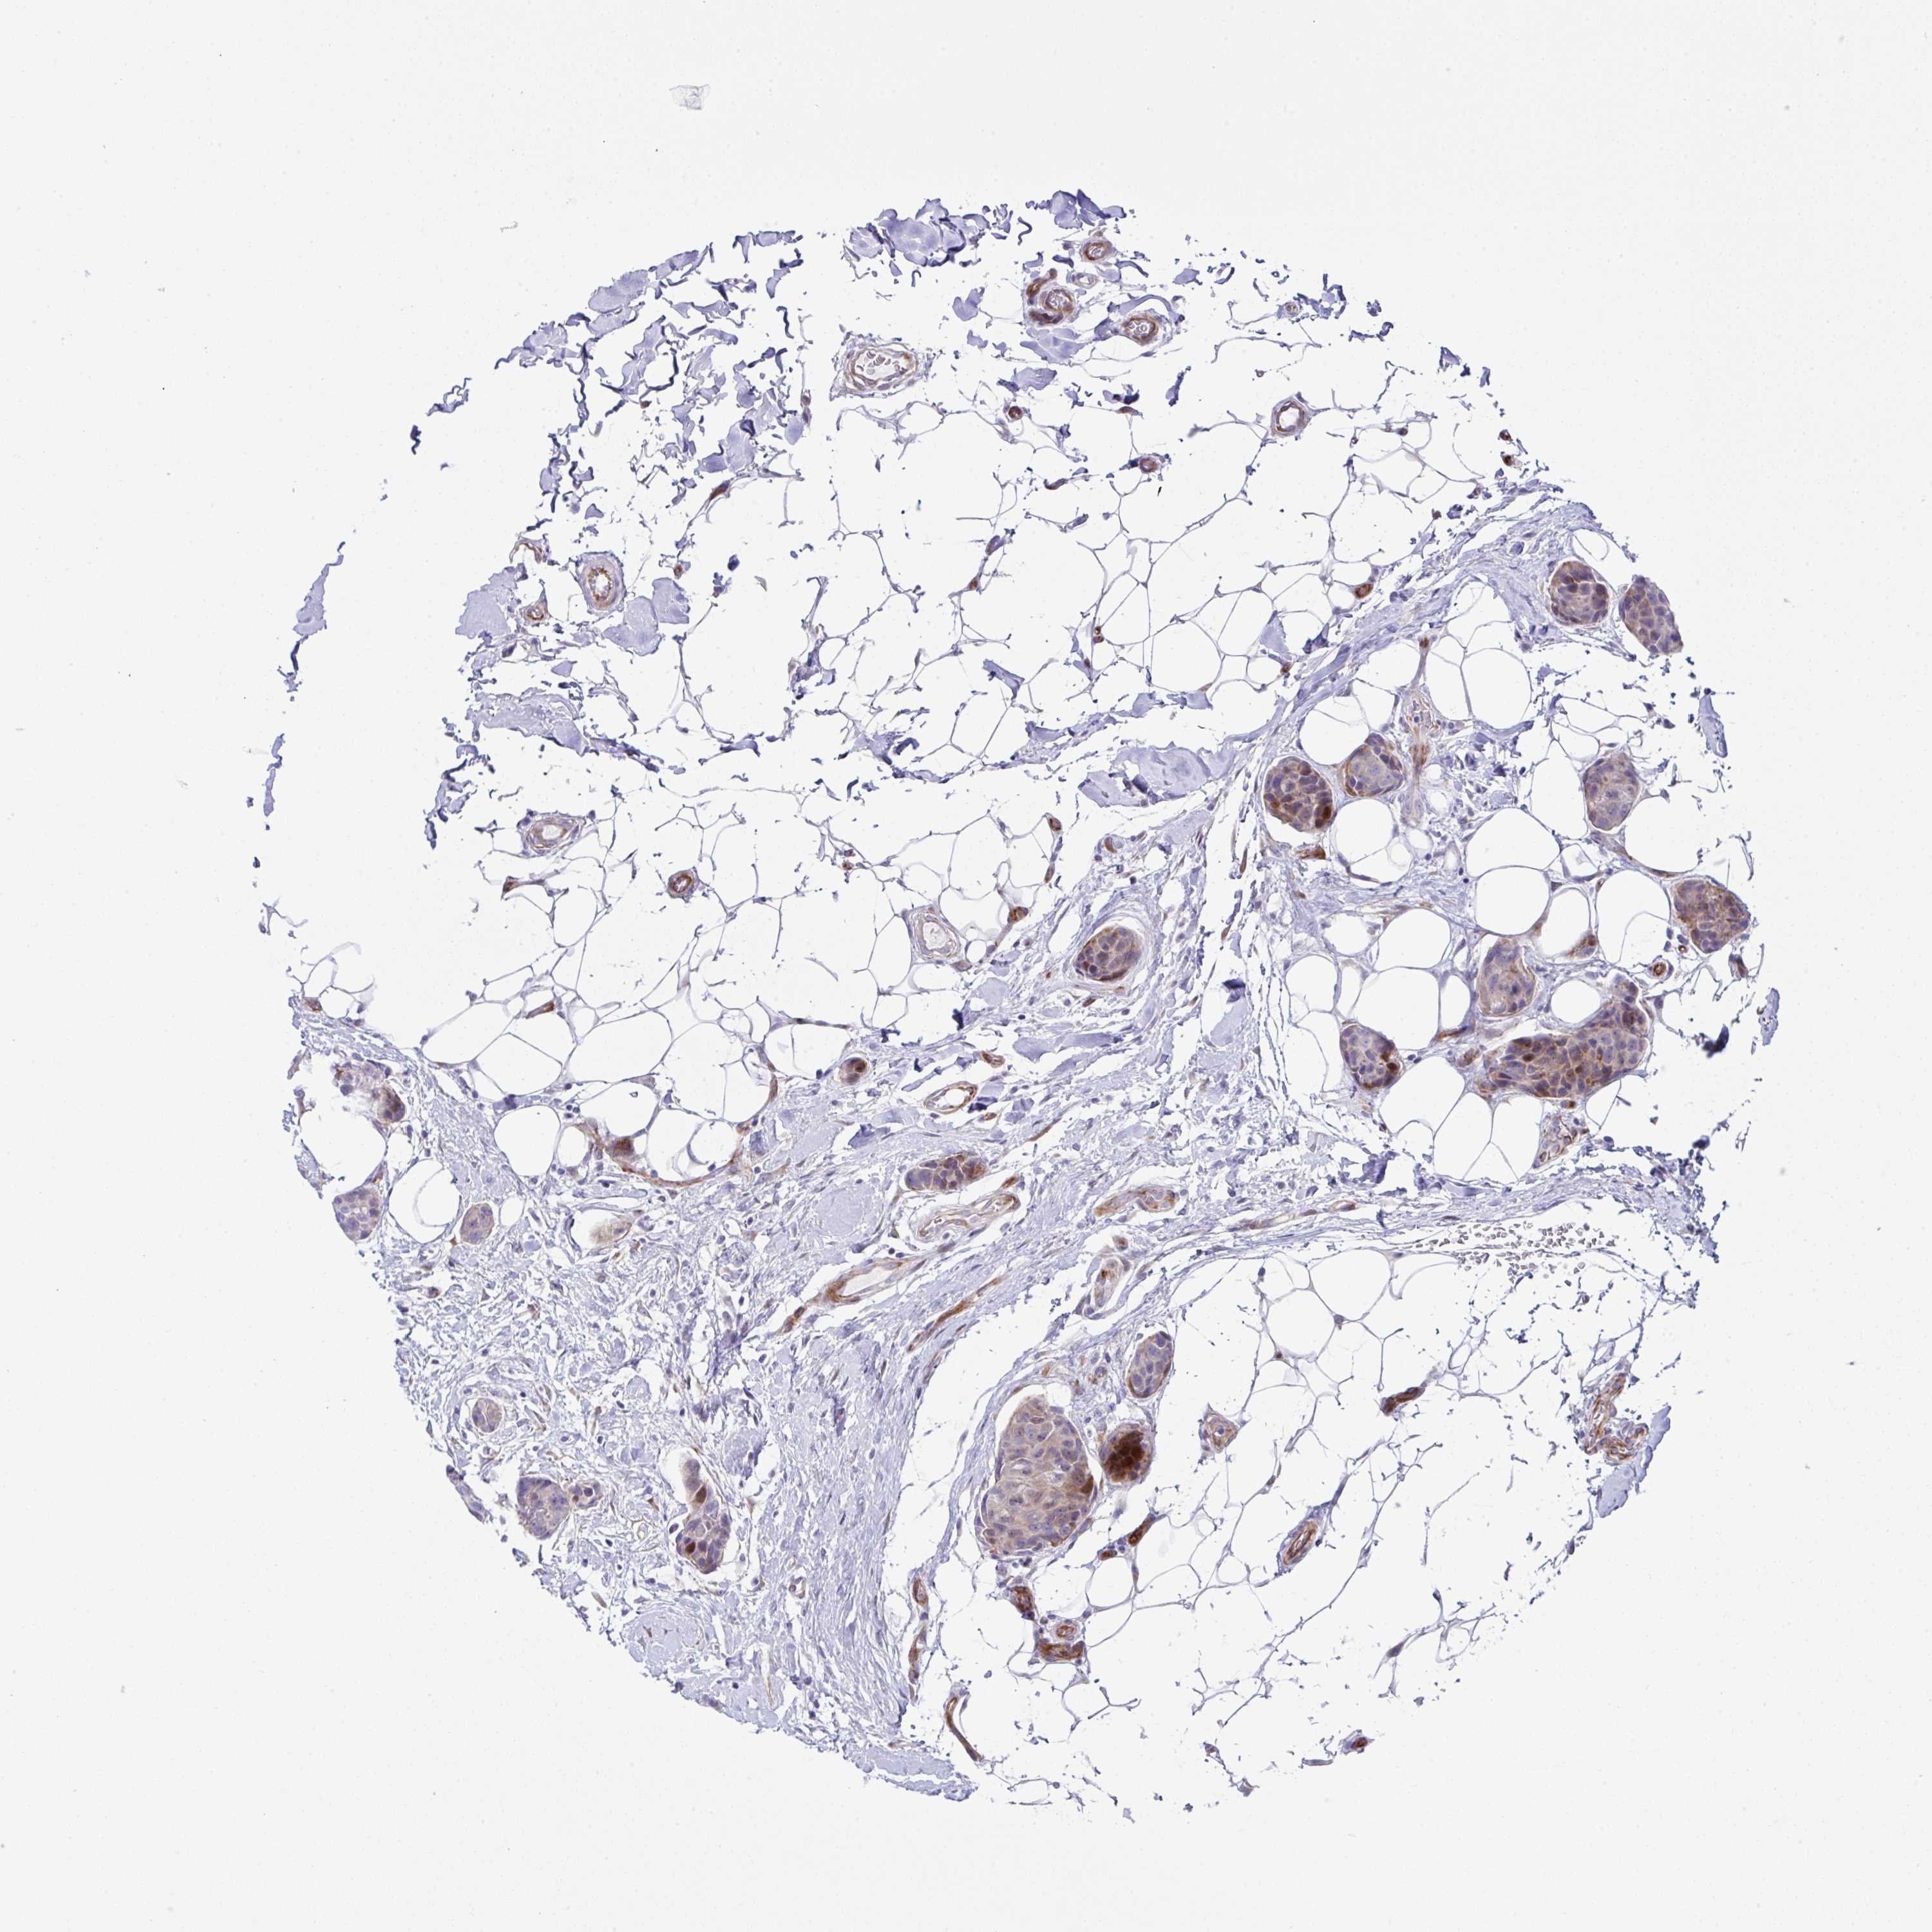

CANCER BREAST CANCER Show tissue menu

BRCA TCGA BRCA VALIDATION PROTEIN EXPRESSION

ANTIBODIES

AND

VALIDATION